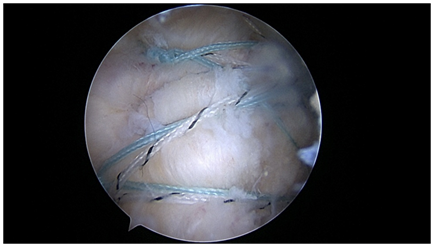

Biceps tenodesis (Figure 8): Arthroscopic supra pectoral approaches to biceps tenodesis that release the sheath are an option for biceps tenodesis, likely because pain relief may be provided by releasing the biceps sheath.24,31 A transosseous approach in this setting reduces anchor use, and obviates the use of a potentially troublesome wound in the axilla. Bone in this area is the most robust in the proximal humerus, and thus readily accessible for strong fixation in anchorless techniques.

Figure 8 Biceps tenodesis: All transosseous suprapectoral biceps tenodesis with tendon grasping sutures.

The biceps may be released, or initially left in situ for this technique. We prefer to release the biceps to allow for an interesting tendon grasping repair. Two tunnels are created with an awl from an anterolateral portal after releasing the biceps sheath. The first tunnel is created from the same portal in the inferior position, just at the superior margin of the pectorals major and above the anterior circumflex vessels. The doubled suture is retrieved through the tendon from an accessory inferomedial portal, and a locking loop is formed utilizing a retrograde passing device. This suture loop is then locked with the lateral suture tail and tied arthroscopcially with the biceps at physiological length from a posterior arthroscopic grasper. The second, more superior tunnel is then created using the arthroscopic tunneler. This double passing suture is then brought through the tendon using a retrograde passing device from the inferomedial portal. Grasping instruments are used to pass the loop over the tendon, creating a strong circumferential grasp on the tendon. The retrograde device is then used to create another locking loop through the circumferential loop, creating excellent fixation with a “cinch loop configuration”. These sutures are then tied arthroscopically with the post lateral. The remaining tendon is removed, and the tendon ends are annealed with the electrocautery.32-38